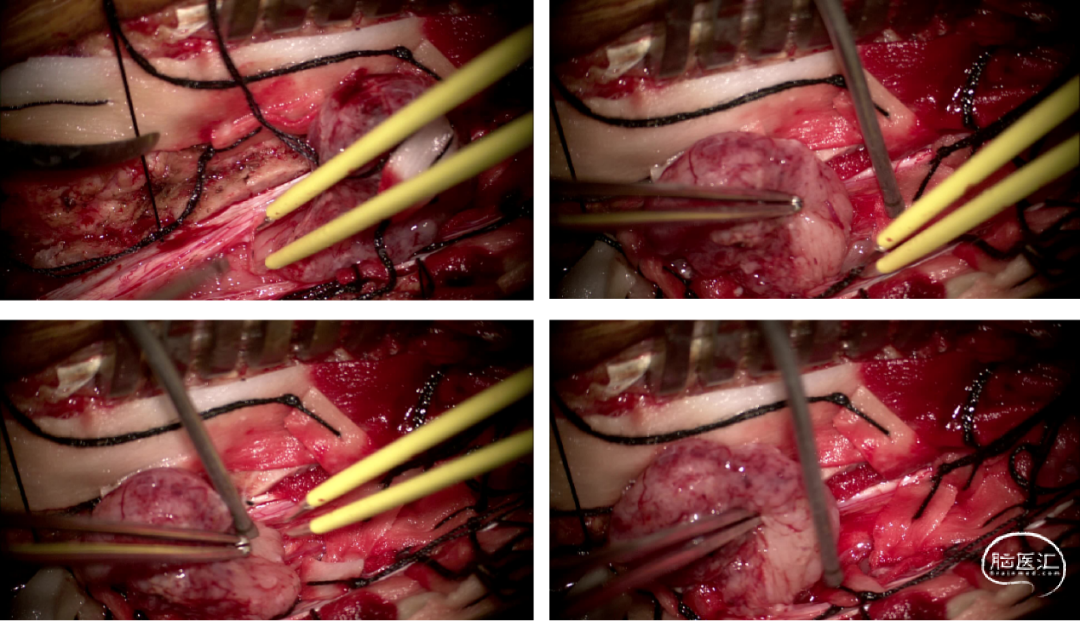

手术情况

硬脊膜张力高,脊髓向背侧膨出,与脊髓腹侧粘连紧密,肿瘤挤压脊髓,肿瘤边界分离,减少对胸髓的牵拉,降低了术后患者神经功能发生的概率,术后患者肢体麻木症状改善。